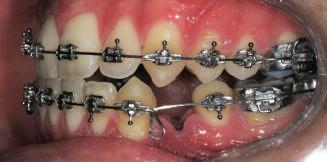

20 Dental Tribune Bulgarian Edition / октомври 2022 г. П ациентите със завършен растеж и скелетни проблеми обикновено представляват предизвикателство за ортодонт ската практика. Необходимостта от изваждане на зъби в комбинация с особеностите на възрастовата ортодонтия изисква особено внима ние. Фокусът върху критично важното значение на позицията на долните резци във връзка с дългосроч ната стабилност и постигането на оптимални оклузални взаимоотношения при затварянето на екстракционните пространства лесно може да излезе извън контрол. Когато към тези чисто кли нични проблеми се добави и стресът от натоваре ната практика, предизвикателството става още по-голямо. Всички тези фактори налагат използ ването на доказан подход с ясни и последовател ни стъпки, в което се разкрива силата на дисциплината „Алекзандър“ – предвидим протокол през целия процес на елиминиране на ротациите, ниве лиране на дъгите, затваряне на екстракционните пространства и финализиране на случая. Именно такъв е и случаят, който презентираме –екстракционен, скелетен клас 3 при възрастен па циент, лекуван по системата „Алекзандър“. ПРЕДВИДИМИ РЕЗУЛТАТИ ПРИ ПАЦИЕНТИ СЪС ЗАВЪРШЕН РАСТЕЖ И СКЕЛЕТЕН КЛАС 3, ИЗПОЛЗВАЙКИ ЕКСТРАКЦИОННО ЛЕЧЕНИЕ ПО ДИСЦИПЛИНАТА „АЛЕКЗАНДЪР“ Д-р Радой Димитров, България Преди започване на лечение клиничен случай | ортодонтия Фиг. 1а–1e Преди започване на лечение. Пациентът пристига в практиката с основното оплакване от невъзмож ност за нормално дъвчене. Снета е цялата необходима диагностична ин формация. Фиг. 1f–1h Снимки в профил и анфас. Фиг. 1i–1k Панорамна снимка, телерентгенография и анализ на телерент генография. Фиг. 1а Фиг. 1d Фиг. 1f Фиг. 1g Фиг. 1h Фиг. 1e Фиг. 1b Фиг. 1c Фиг. 1i Фиг. 1j Фиг. 1k

closed.

21Dental Tribune Bulgarian Edition / октомври 2022 г. ДИАГНОСТИЧНИ РЕЗУЛТАТИ: 1. Възраст на пациента: 21 години 2. Скелетен клас III (ANB 0) 3. Зъбен клас 3 4. Ръбцова захапка във фронта, кръстосана в дисталните участъци 5. Тясна горна челюст 6. Overjet – 0 мм, Overbite – 0 мм 7. Несъответствие на горната с долната средна линия 8. Единични контакти в ЦО 9. Хиподивергентен тип на растеж SN/MP – 33.5 10. Неравен гингивален контур 11. Неравна линия на усмивката 12. Тенденция за рецесии в долен фронт ПРЕПОРЪЧИТЕЛНО ЛЕЧЕНИЕ: Пълно ортодонтско лечение с метални брекети „Алекзандър“ Корекция на клас 3 захапката в областта на кучешките зъби с екстракция на първите пре молари в долна челюст Корекция на кръстосаната захапка в дистални участъци Коригиране на ръбцовата захапка във фронта Подобряване на ОJ и OB на пациента Стрипинг в долен фронт Подреждане на зъбите в горната и долната челюст Професионално хигиенизиране и профилактични дентални прегледи са препоръчителни на всеки 6 месеца. 1-ви месец След 1 месец са залепени брекети в горната челюст – поставена е еластична дъга. 016 NiTi. В долната челюст са елиминирани ротациите, поставена е стоманена дъга. 016SS, закалена с ток, и еластична верижка за затваряне на пространствата. 3-ти месец В долната челюст е поставена трета дъга – 17 x 25 NiTi с къси лигатури и верижка

В горната челюст се затварят пространствата с дъга .016SS и верижка. 5-и месец На 5-ия месец след залепяне на брекетите в долната челюст е поставена стоманена дъга 16 x 22 SS с четвъртито сечение, омега луп и тай бек. В горната челюст е поставена дъга 17 x 25 NiTi. Поради липсата на стабилни оклузални контакти са поставени лингвални верижки в областта на моларите, за да се предотврати нежелана ротация на 7-ите зъби. 6-и месец На 6-ия месец от началото на лечението са екстрахирани долните първи премолари, поставена е дъга 16 x 22 SS със затваряща чупка teardrop. Чупката се активира всеки месец по 1 мм с чинч-бек. клиничен случай | ортодонтия СТЪПКИ НА ЛЕЧЕНИЕТО Начало на лечението Лечението започва с поставяне на апарат за бърза експанзия в горната челюст. През първия месец от лечението са направени 24 оборота на апарата за експанзия. Залепени са брекети в долната челюст, поставена е дъга 17x25 CuNiTi, като са предпи сани клас 3 ластици (1/4”,4 1/2 oz) по време на сън, за да се осигури контрол върху торка на долните резци. Фиг. 2а Фиг. 3a Фиг. 4a Фиг. 3b Фиг. 4b Фиг. 3c Фиг. 4c Фиг. 3d Фиг. 4d Фиг. 3e Фиг. 4e Фиг. 5a Фиг. 5b Фиг. 5c Фиг. 5d Фиг. 5e Фиг. 6a Фиг. 6b Фиг. 6c Фиг. 6d Фиг. 6e Фиг. 7a Фиг. 7b Фиг. 7c Фиг. 7d Фиг. 7e Фиг. 2b Фиг. 2c Фиг. 2d